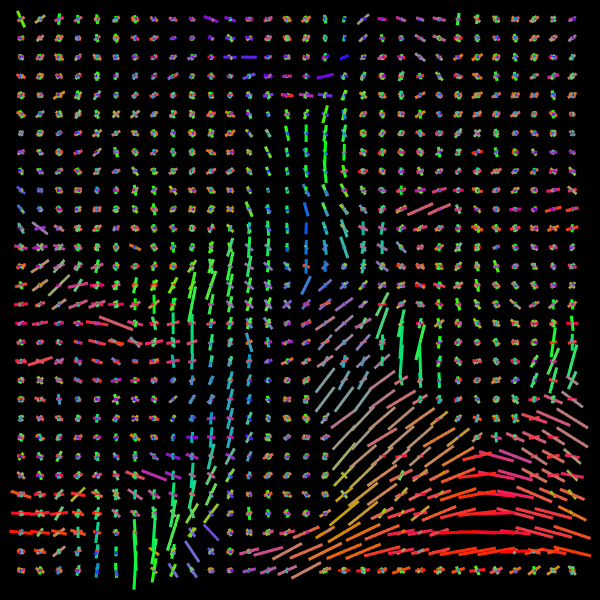

Training stage. We compare the results of the proposed Voxel (VOX) and Neighborhood (NBH) models with two of the SOTA methods which tackle the same task: Diffusion Basis Functions (NNLS) proposed by Ramirez-Manzanares et al. (2007)) and Constrained Spherical Deconvolution (CSD) proposed by Tournier et al. (2007). There are many options to compare distributions, a common comparisson procedure used in this context is to detect peaks and compute the angular error between the real peaks and the estimated ones. However, to compare modes in not a standard procedure for comparing distributions. Among them two notable options are Kullback-Leibler (KL) Divergence and the Wasserstein Distance (also know as the Earth Mover Distance, EMD). Despite its computational cost, EMD has shown to represents more precisely the distribution distance (Levina and Bickel, 2001; Aranda et al., 2011; Arjovsky et al., 2017). EMD represents the minimum cost of transforming a peak distribution into another, weighting by angle. We create a synthetic dataset with gradient table of the Stanford HARDI dataset (Rokem et al., 2015), the eigenvalues of a Diffusion Tensor model fitted to the corpus callosum region, and the SNR computed in such a data (Descoteaux et al., 2011). The estimated SNR depends on image region: most of the measures laid into [20,24]2024[20,24], so we randomly generate data selecting the SNR into [20,30]2030[20,30]. Figure 5 depicts the error for each analyzed model. The vertical axis corresponds to the angle (θ1subscript𝜃1\theta_{1}) between the first PDD and the second one. Meanwhile, the horizontal axis shows the angle between the third PDD and the plane formed by the first two PDDs. The dynamic range of the error maps shows a better performance of the proposed models. We select some predictions for a visual inspection (qualitatively comparison). For illustration purposes, we choose one between the top–101010 and one of the bottom–101010 according to its EMD values for the studied models: VOX, NBH, NNLS, and CSD. The results are presented in Figure 6. The first two columns correspond to the best predictions: the first column shows the target and the second column shows the prediction. The third and fourth columns follow the same order but for the worst predictions. Arrows illustrate the generated PDDs (ground truth). According to the α𝛼\alpha value: blue, orange, and green were used for the first, second, and third PDD, respectively.

Refer to caption

Figure 6: Predicted voxels with lowest (first two columns) and highest error (last two columns).